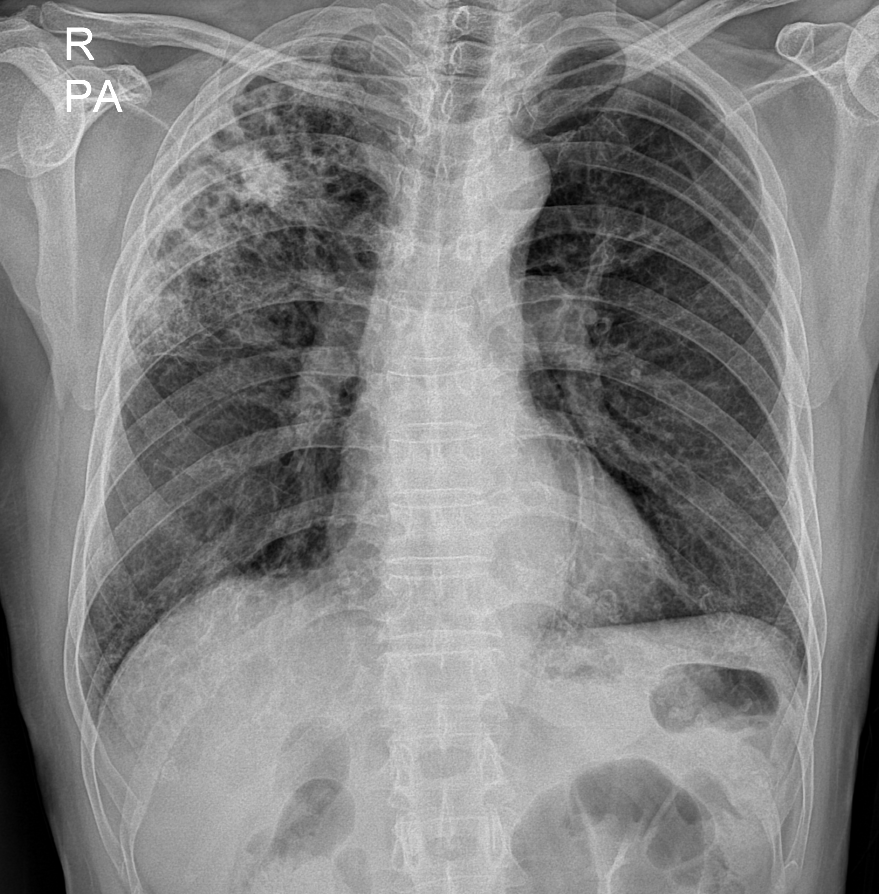

66세 여성

왼쪽부터 우상엽/하엽 폐렴 진단 당시의 흉부 엑스레이, 치료 4일째, 치료 1주째